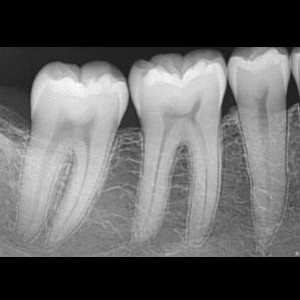

SERVICIOS 2D